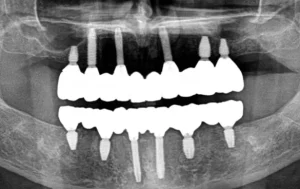

ET III is a brand of dental implants designed to provide reliable and long-lasting tooth replacement solutions. Dental implants like ET III serve as artificial

KAT Implants represent a modern dental implant system designed to restore missing teeth with precision, durability, and versatility. The innovation behind KAT Implants lies in